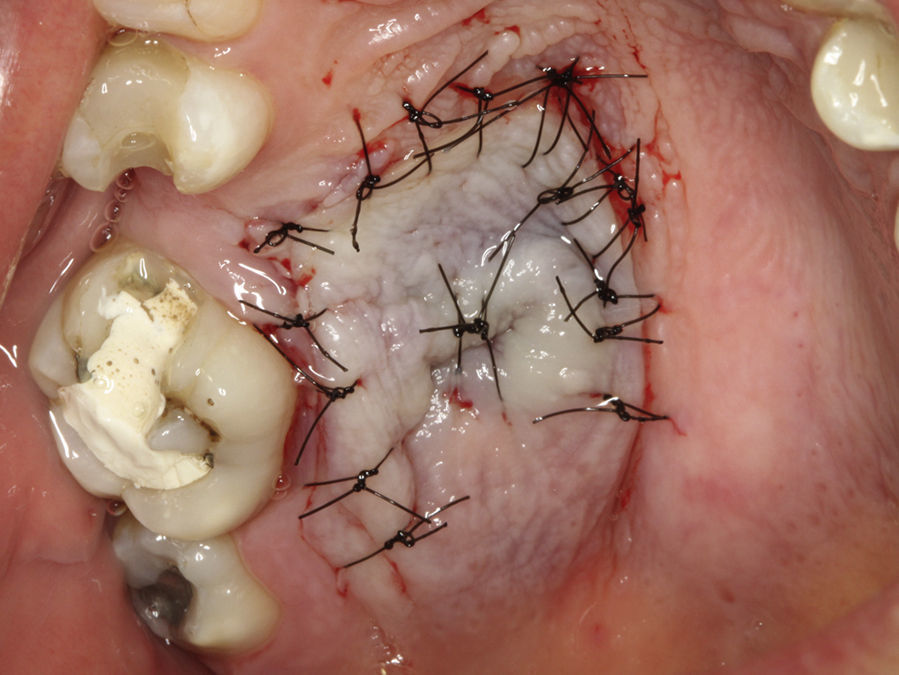

Casos clínicosCaso 1Paciente do sexo masculino, 68 anos de idade, leucoderma, procurou a Clínica de Estomatologia do Departamento de Odontologia da Pontifícia Universidade Católica de Minas Gerais (PUC Minas) queixando‐se de aumento de volume no palato, com tempo de evolução de 2 anos e discreta sintomatologia dolorosa. A anamnese não revelou alterações sistémicas. Ao exame clínico extraoral não foram observadas alterações. O exame clínico intraoral mostrou lesão nodular, pediculada, de consistência firme, localizada no palato duro do lado direito, entre os pré‐molares superiores e a rafe palatina, medindo aproximadamente 2cm na sua maior extensão. Foi realizada uma radiografia oclusal de maxila que não mostrou alterações ósseas. As hipóteses diagnósticas de neoplasia de glândula salivar e neoplasia mesenquimal benigna foram consideradas. Foi realizada biópsia incisional com diagnóstico anatomopatológico de adenoma pleomórfico. O tratamento proposto para a lesão foi a remoção cirúrgica conservadora. Paciente retornou após 4 semanas exibindo, ao exame intraoral, ulcerações na mucosa que recobria a lesão (fig. 1). Inicialmente, foi realizada anestesia local por meio da técnica supraperiosteal para bloqueio de ramos do nervo palatino maior, com cloridrato de lidocaína 2% e epinefrina 1:100.000 (ALPHACAINE 100®, DFL, Rio de Janeiro, Brasil). Em seguida, foi realizada incisão na base da lesão com bisturi lâmina 15 (Solidor, São Paulo, Brasil) e, após o descolamento do retalho mucoso palatino, a lesão foi exposta e removida (fig. 2). Foi realizada limpeza da ferida cirúrgica e sutura com fio seda Ethicon™ 4.0 (Johnson & Johnson, São Paulo, Brasil) (fig. 3). A lesão excisada (fig. 4) foi fixada em solução de formaldeído a 10% e enviada para exame anatomopatológico no Laboratório de Patologia Bucal da PUC Minas.